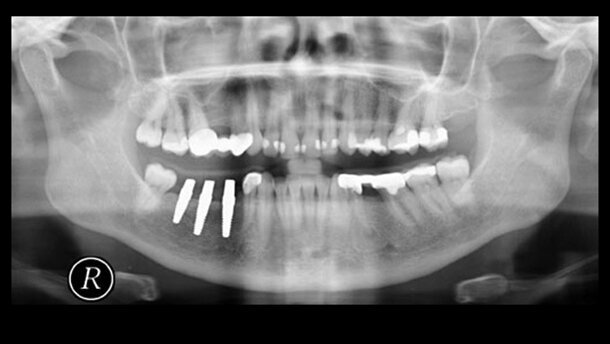

Abb. 3a: Röntgenmessaufnahme einer 47-jährigen Patientin mit Schaltlücke 44–48 (v.l.n.r.). Abb. 3b: Intraoperativer Situs. Abb. 3c: Nahtversorgung. Abb. 3d: Schienenprovisorium.

Abb. 3e: Postoperative Röntgenkontrolle (v.l.n.r.). Abb. 3f: Kontrolle nach drei Monaten. Abb. 3g: Kontrolle in Okklusion nach drei Monaten. Abb. 3h: Schienenkontrolle nach drei Monaten.Diskussion